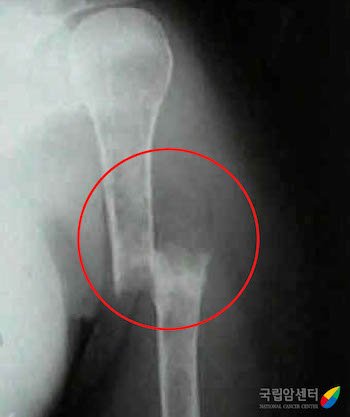

[ 다발골수종 환자에서 발생한 위팔뼈의 골절(X ray) ]

다발골수종은 환자들마다 증상의 차이가 있으나 가장 흔한 대표적인 증상으로는 빈혈, 뼈 통증, 신장 수치 상승, 및 고칼슘 혈증이 있습니다. 빈혈은 다발골수종의 원인이 되는 형질세포의 골수 내 증식에 의하며 이로 인한 피로감, 어지러움 및 호흡 곤란 등의 증상이 발생할 수 있습니다. 뼈의 통증 및 골절 역시 다발골수종의 가장 흔한 증상 중의 하나이며 특히 척추뼈의 압박 골절이 발생하는 경우 허리 통증 외에도 하지 마비 등의 신경학적 증상이 동반될 수 있습니다. 고칼슘 혈증으로 인한 구역감, 변비, 의식 및 정서 상태의 변화가 유발될 수 있으며, 신장 기능 저하로 인한 혈액 검사상 신장 수치의 상승 및 단백뇨가 발생할 수 있습니다. 또한 면역 기능의 저하로 인한 감염 증상 및 응고 인자 기능 저하로 인한 출혈 증상도 다발골수종에서 보일 수 있는 증상에 속합니다.

다발골수종은 주로 골수에서 발생하는 혈액암의 일종이나 간혹 골수를 둘러싸고 있는 뼈나 기타 여러 장기에서 고형 종양의 형태를 보이는 형질세포종으로 발생하기도 합니다. 특히 뼈에 침범하는 경우가 흔하며 이러한 경우 척추의 통증이나 압박골절 및 이로 인한 하지마비와 같은 신경학적 증상을 유발할 수 있습니다.

다발골수종은 환자들마다 증상의 차이가 있으나 가장 흔한 대표적인 증상으로는 빈혈, 뼈 통증, 신장 수치 상승 및 고칼슘 혈증이 있습니다. 빈혈은 다발골수종의 원인이 되는 형질세포의 골수 내 증식에 의하며 이로 인한 피로감, 어지러움 및 호흡 곤란 등의 증상이 발생할 수 있습니다. 뼈의 통증 및 골절 역시 다발골수종의 가장 흔한 증상 중의 하나이며 특히 척추뼈의 압박 골절이 발생하는 경우 허리 통증 외에도 하지 마비 등의 신경학적 증상이 동반될 수 있습니다. 고칼슘 혈증으로 인한 구역감, 변비, 의식 및 정서 상태의 변화가 유발될 수 있으며, 신장 기능 저하로 인한 혈액 검사상 신장 수치의 상승 및 단백뇨가 발생할 수 있습니다. 또한 면역 기능의 저하로 인한 감염 증상 및 응고 인자 기능 저하로 인한 출혈 증상도 다발골수종에서 보일 수 있는 증상에 속합니다.